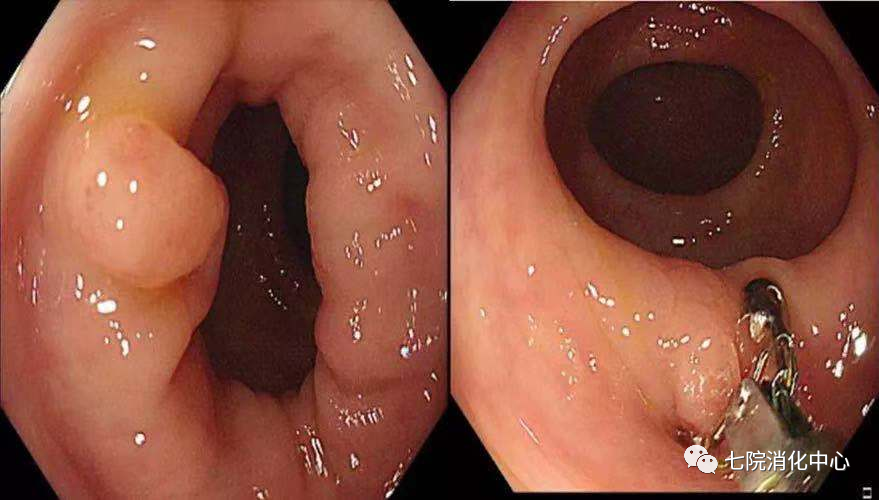

王阿姨今年65岁,前段时间总感觉肚子不舒服,大便带血,每天的排便习惯也有改变,于是来到交大附属胸科医院消化中心就诊,接诊的消化科副主任张蓉在了解其病情后,将其收治入院。入院后肠镜检查发现,其肠道内多发大小不等息肉,最大直径1.8cm.医生当即对息肉进行了切除处理,病理提示管状绒毛状腺瘤伴低级别上皮内瘤变,但庆幸的是发现较早,目前王阿姨已经康复出院,之后只需要每半年复查一次肠镜。

内镜下切除治疗已成为处理结肠息肉的主要手术方式,其具有操作简便、安全、创伤性小等优势,目前在临床得到广泛推广;了解每种手术方式的优势和风险,选择合适的手术方式,更能减少术中、术后风险,使患者获益。

包括冷活检钳息肉切除术和热活检钳息肉切除术,活检钳通常用于切除5mm以下的结肠息肉。

圈套器分为冷圈套器和热圈套器。

①热圈套器息肉切除术:基本原理是如果有足够的电流通过,产生的热量使细胞破裂导致组织被切割。对于小型息肉切除术,不建议热圈套器,因为它们有发生热不良事件的风险。建议热圈套器用于10~19mm带蒂息肉,因带蒂息肉的茎部具有穿透性血管,要求某种形式的预防止血。热圈套器息肉切除术引起的烧灼是防止立即出血的一种手段。

②冷圈套器:具有切除整个息肉的能力,避免了零碎的切除,并且可用于在同一过程中发现的较大息肉。其优点是可以防止电灼引起的对黏膜下血管组织的损害,并且对患者术后活动或饮食的限制较少。因为在冷圈套器息肉切除术期间不使用电灼,其术后出血和穿孔的发生率较低。